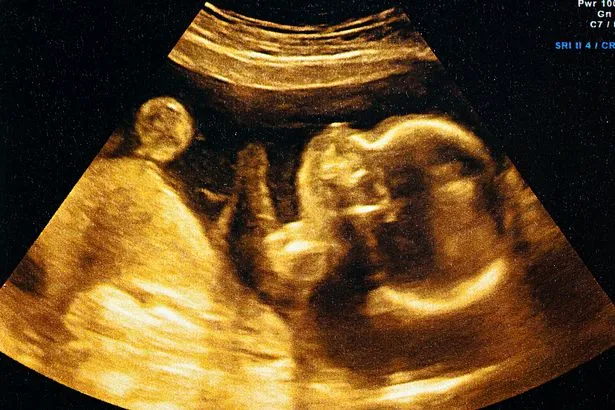

Our expert, Dr. Neha Gupta, is a highly qualified fetal medicine specialist. She has many years of experience in doing ultrasounds during pregnancy. She is not only trained in detection of abnormalities in the unborn child but will also counsel you how to approach further in the pregnancy. She is experienced in counseling the families in whom the future pregnancies (the unborn child) are at risk of developing hereditary diseases or helping those women who have some medical disorders which can affect the baby in the womb.